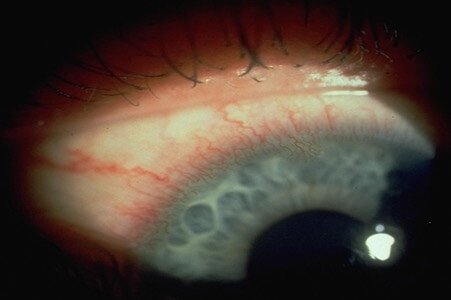

眼紅

眼白通紅,主要是因為結膜上的微絲血管擴張,代表眼球需要更多血液去作出修復或提供養份,有些個案更會發展至角膜血管增生,長遠對視力造成影響。“紅筋”的成因有很多:配戴隱形眼鏡鏡片的透氧度、配戴時間長短、鏡片度數弧度、淚水不足、眼睛表面傷口、敏感反應等等。正正因為背後的原因太多,如隱形眼鏡配戴者發覺問題嚴重,應立即停用隱形眼鏡,觀察情況有否改善,並盡早諮詢您的眼科視光師,以聽取適當的改善建議。

眼紅

照片由香港理工大學眼科視光學院提供

血管擴張

照片由香港理工大學眼科視光學院提供